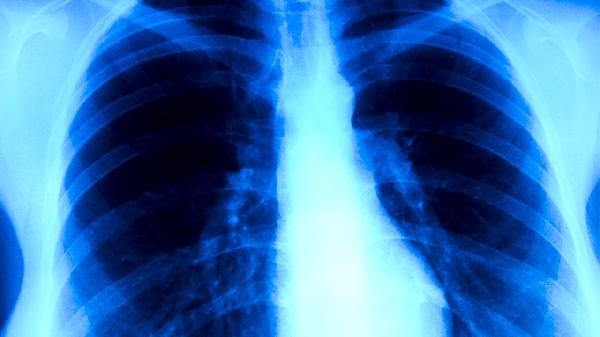

肺结核患者可遵医嘱使用异烟肼片、利福平胶囊、吡嗪酰胺片、乙胺丁醇片、链霉素注射液等抗结核药物。肺结核是由结核分枝杆菌感染引起的慢性传染病,需规范联合用药以杀灭病原体并防止耐药性产生。